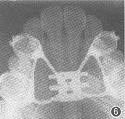

牵引成骨术是利用Ilizarov[8]的牵引成骨理论,利用骨牵引器在截开的两个骨端间逐渐打开骨段,并促使骨断端间骨的生成。本组中10例成人上颌牙弓宽度不足者,上颌骨的扩大量最大达到8.05 mm,磨牙最大扩大量达到8.34 mm。由于解除了上颌骨周围和腭中缝处的阻力,不致使上颌后牙颊向倾斜。一般打开的骨缝处2周即可开始出现骨沉积,4~6周时新骨开始钙化,约2~3个月新骨改建完成(图6~8)。因此,牵引成骨完成扩大上颌牙弓后,宜以自凝塑料封闭原扩弓器螺旋,继续保持3个月,以防止畸形复发。

图6 扩弓前上颌前部咬合片

图7 扩弓后上颌前部咬合片

图8 扩弓完成保持3个月后上颌前部咬合片